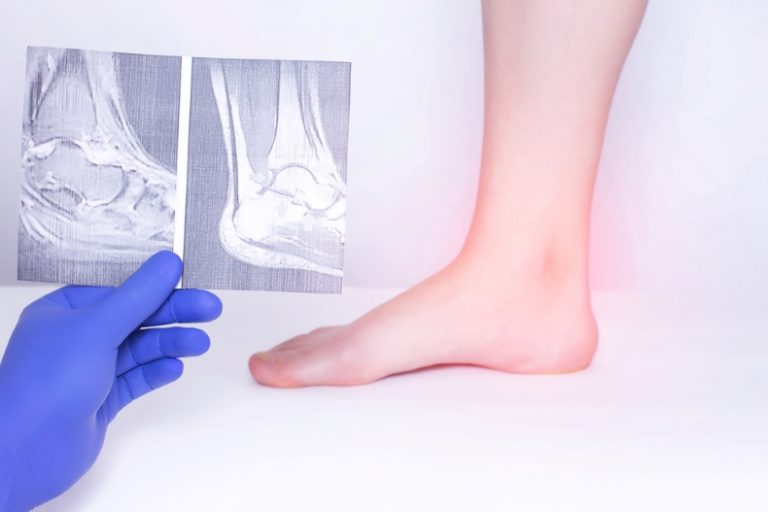

In most cases, many doctors emphasize that it is possible to perform what is known as autografting. This type of procedure depends on choosing the source of the bone graft, which is based on various factors related to size, shape, strength, the ability to stimulate recovery and healing. Some of the prominent places where autografts can be obtained include:

- Pelvic bones.

- Shins.